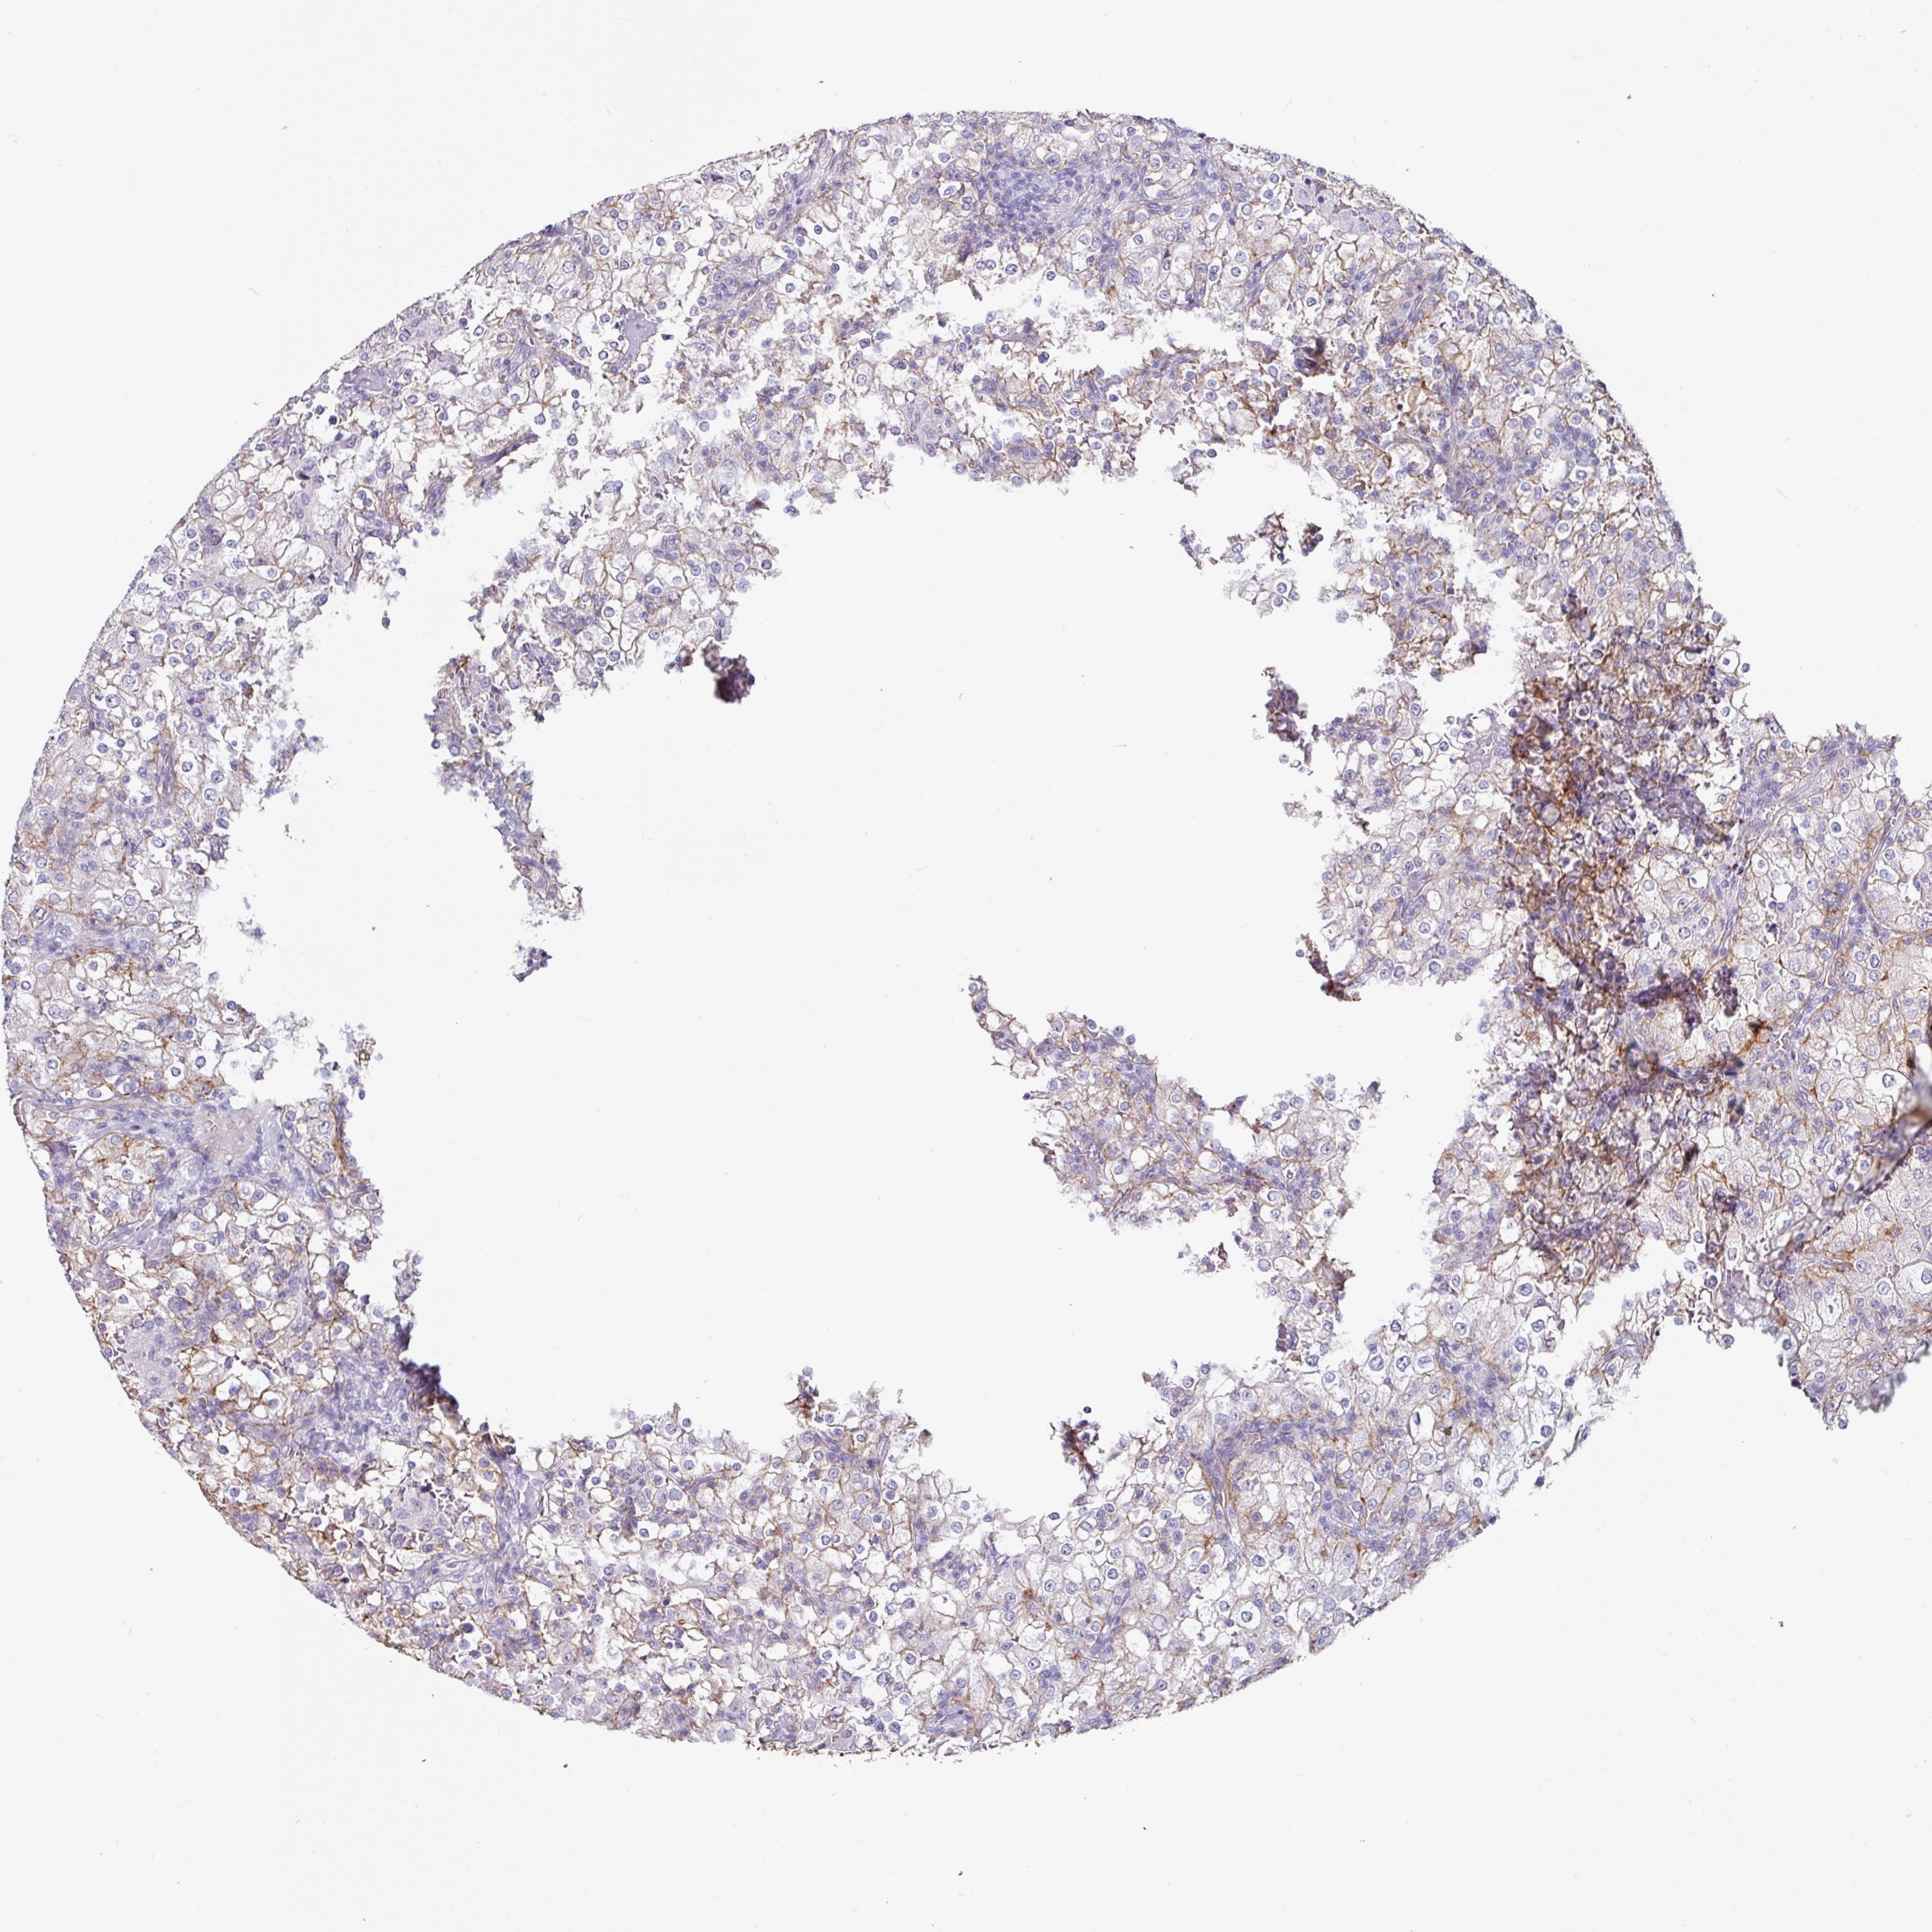

KIDNEY RENAL CLEAR CELL CARCINOMA (VALIDATION) - Interactive survival scatter ploti

The Survival Scatter plot shows the clinical status (i.e. dead or alive) for all individuals in the patient cohort, based on the same data that underlies the corresponding Kaplan-Meier plots. Patients that are alive at last time for follow-up are shown in blue and patients who have died during the study are shown in red.

The x-axis shows the expression levels (FPKM) of the investigated gene in the tumor tissue at the time of diagnosis. The y-axis shows the follow-up time after diagnosis (years). Both axes are complimented with kernel density curves demonstrating the data density over the axes. The top density plot shows the expression levels (FPKM) distribution among dead (red) and alive patients (blue). The right density plot shows the data density of the survived years of dead patients with high and low expression levels respectively, stratified using the cutoff indicated by the vertical dashed line through the Survival Scatter plot. This cutoff is automatically defined based on the FPKM cutoff that minimizes the p-score. The cutoff can be changed by dragging the vertical line or by entering a cutoff value in the square labeled "Current cut-off".

Under the Survival Scatter plot the p-score landscape (black curve; left axis) is shown together with dead median separation (red curve; right axis). Dead median separation is the difference in median mRNA expression between patients who have died with high and low expression, respectively. It is calculated as follows: median FPKM expression of dead patients with high expression - median FPKM expression of dead patients with low expression. This is intended to aid the user in visually exploring custom cutoffs and the associated p-scores and dead median separation.

Individual patient data is displayed and can be filtered by clicking on one or more of the category buttons on the top of the page. Categories describing expression level and patient information include: high, low, alive, dead, female, male and tumor stages. The scale of the x-axis can be toggled between linear and log-scale by clicking on the "x log" button. Mouse-over function shows TCGA ID, patient information and mRNA expression (FPKM) for each patient.

& Survival analysisi

Kaplan-Meier plots summarize results from analysis of correlation between mRNA expression level and patient survival. Patients were divided based on level of expression into one of the two groups "low" (under cut off) or "high" (over cut off). X-axis shows time for survival (years) and y-axis shows the probability of survival, where 1.0 corresponds to 100 percent.

JUP is validated prognostic, high expression is favorable in Kidney Renal Clear Cell Carcinoma (validation)

Best expression cut offi

Based on the FPKM value of each gene, patients were classified into two groups and association between prognosis (survival) and gene expression (FPKM) was examined. The best expression cut-off refers the FPKM value that yields maximal difference with regard to survival between the two groups at the lowest log-rank P-value. Best expression cut-off was selected based on survival analysis .

When clicking on this number, the vertical dashed line indicating cut-off, the interactive survival plot, and the Kaplan-Meier curve will be adjusted to show results based on the best expression cut-off.

: 90.21

TCGA RNA samplesi

RNA-seq data is reported as average FPKM (number Fragments Per Kilobase of exon per Million reads), generated by the The Cancer Genome Atlas (TCGA) .

Normal distribution across the dataset is visualized with box plots, shown as median and 25th and 75th percentiles. Points are displayed as outliers if they are above or below 1.5 times the interquartile range. FPKM values of the individual samples are presented next to the box plot.

Average pTPM 89.2

Number of samples 100